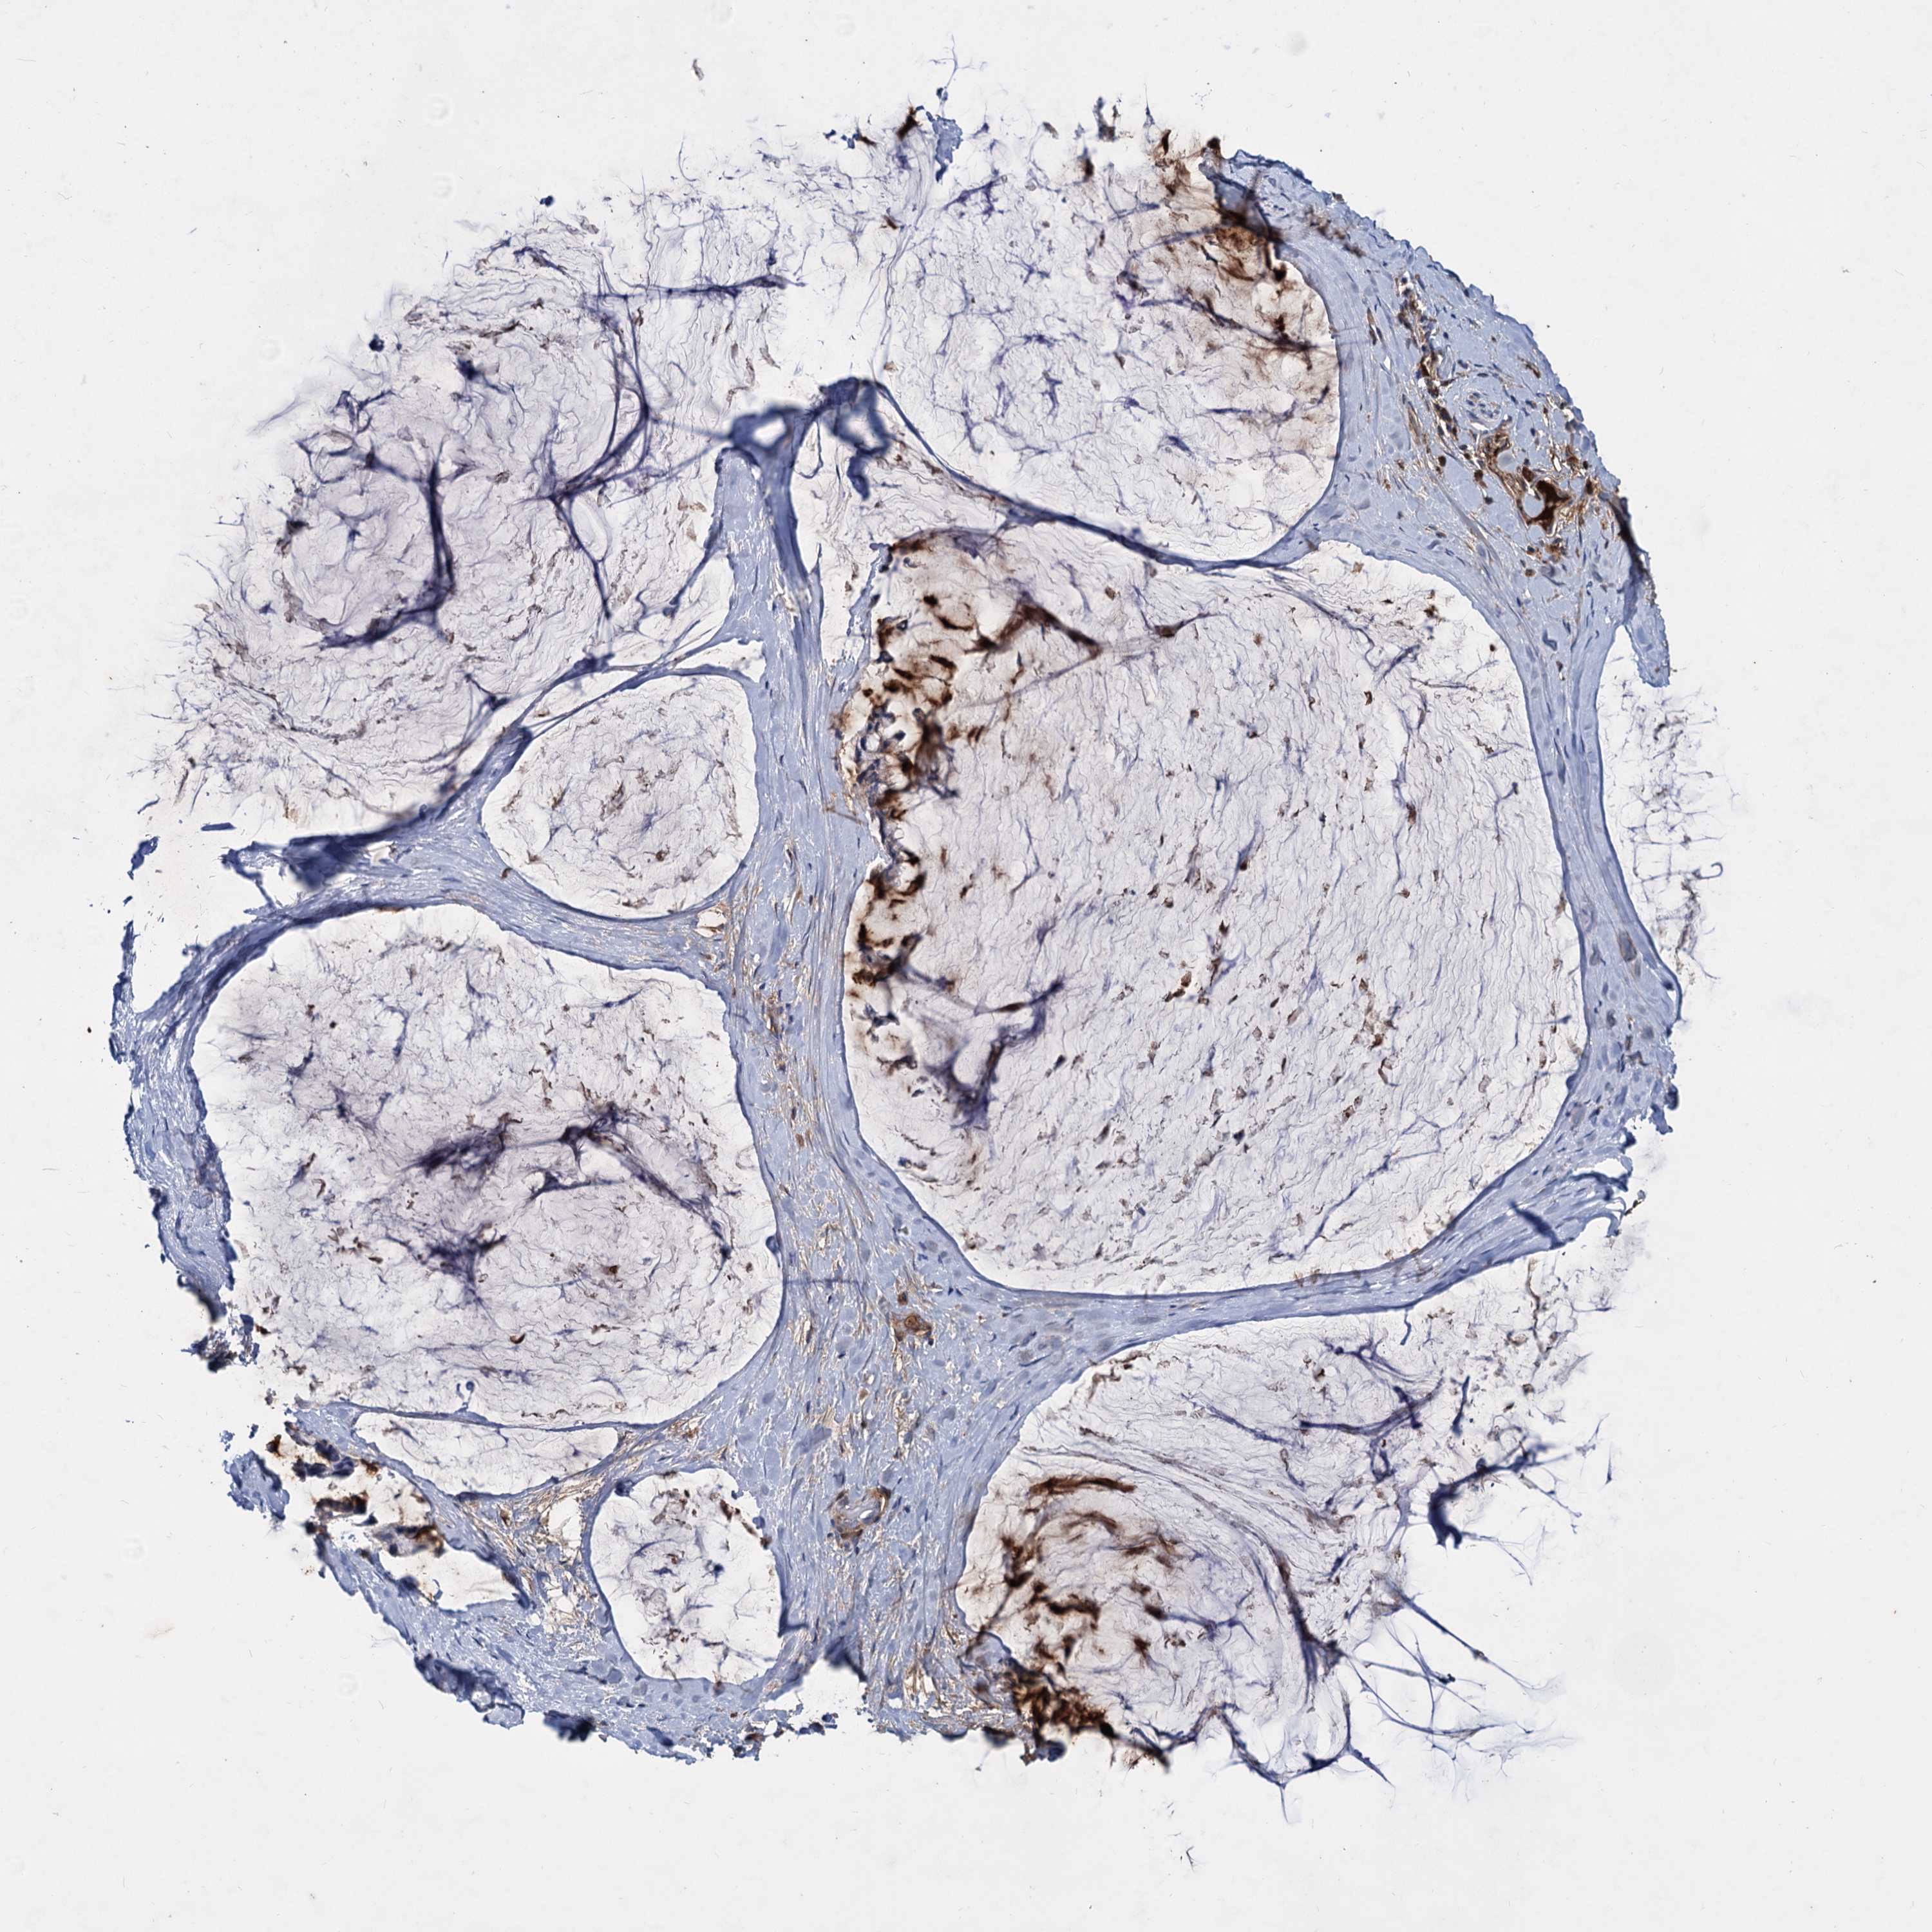

OVARIAN CANCER - Protein expressioni

A mouse-over function shows sample information and annotation data. Click on an image to view it in a full screen mode. Samples can be filtered based on level of antibody staining by selecting one or several of the following categories: high, medium, low and not detected. The assay and annotation is described here.

Note that samples used for immunohistochemistry by the Human Protein Atlas do not correspond to samples in the TCGA dataset.

Antibody stainingi

Antibody staining in the annotated cell types in the current human tissue is reported as not detected, low, medium, or high, based on conventional immunohistochemistry profiling in selected tissues. This score is based on the combination of the staining intensity and fraction of stained cells.

Each image is clickable and will lead to virtual microscopy that enables deeper exploration of all samples and also displays staining intensity scores, fraction scores and subcellular localization as well as patient and tissue information for each sample.

Antibody HPA035827

Staining

High

Medium

Low

Not detected

Intensity

Strong

Moderate

Weak

Negative

Quantity

>75%

75%-25%

<25%

None

Location

Nuclear

Cytoplasmic/membranous

Cytoplasmic/membranous,nuclear

Cystadenocarcinoma, serous, NOS

Carcinoma, endometroid

Cystadenocarcinoma, mucinous, NOS

Carcinoma, NOS